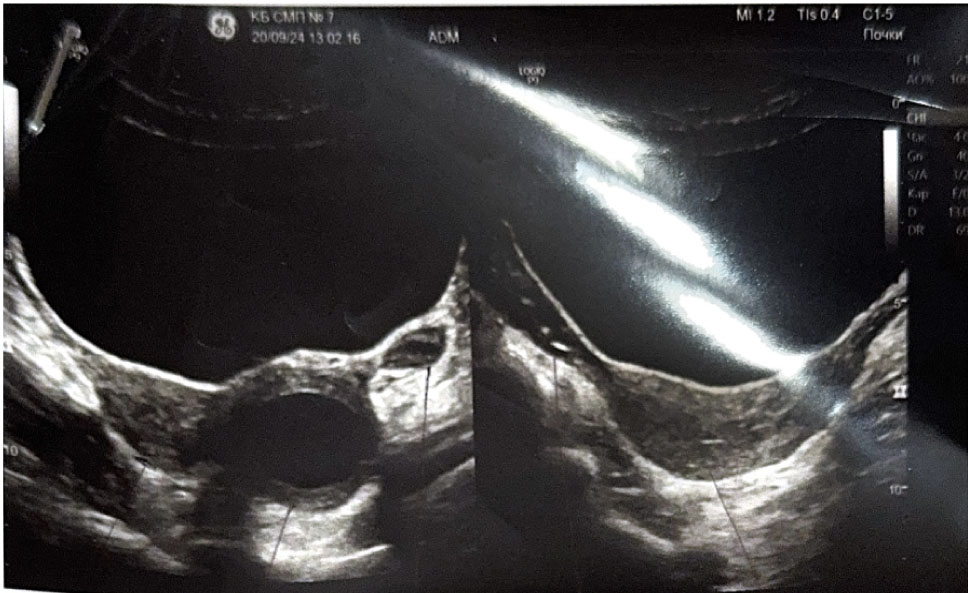

При госпитализации пациентке выполнено УЗИ органов малого таза, выявлено: тело матки смещено вправо, размеры 37 × 26 × 28 мм, миометрий однородной структуры. Толщина эндометрия 3–4 мм, соответствует фазе пролиферации. Правый и левый яичники визуализируются, нормальных размеров без структурных изменений. Слева от матки образование 45 × 42 × 47 мм, средней эхогенности с ровными контурами, соответствует структуре миометрия, толщиной 15–17 мм. В центре образования жидкостной однородный участок, размерами 29 × 30 мм (гематометра?). Выше и каудальнее левого яичника лоцируется тубулярное анэхогенное образование толщиной 4–6 мм протяженностью 30 мм (маточная труба?). Заключение: аномалия развития матки (матка с рудиментарным рогом слева). Гидросальпинкс слева. Гематометра слева (рис. 1, 2).

Рис. 1. Ультразвуковое исследование органов малого таза. Аномалия развития матки

Рис. 2. Ультразвуковое исследование органов малого таза. Рудиментарный замкнутый рог матки